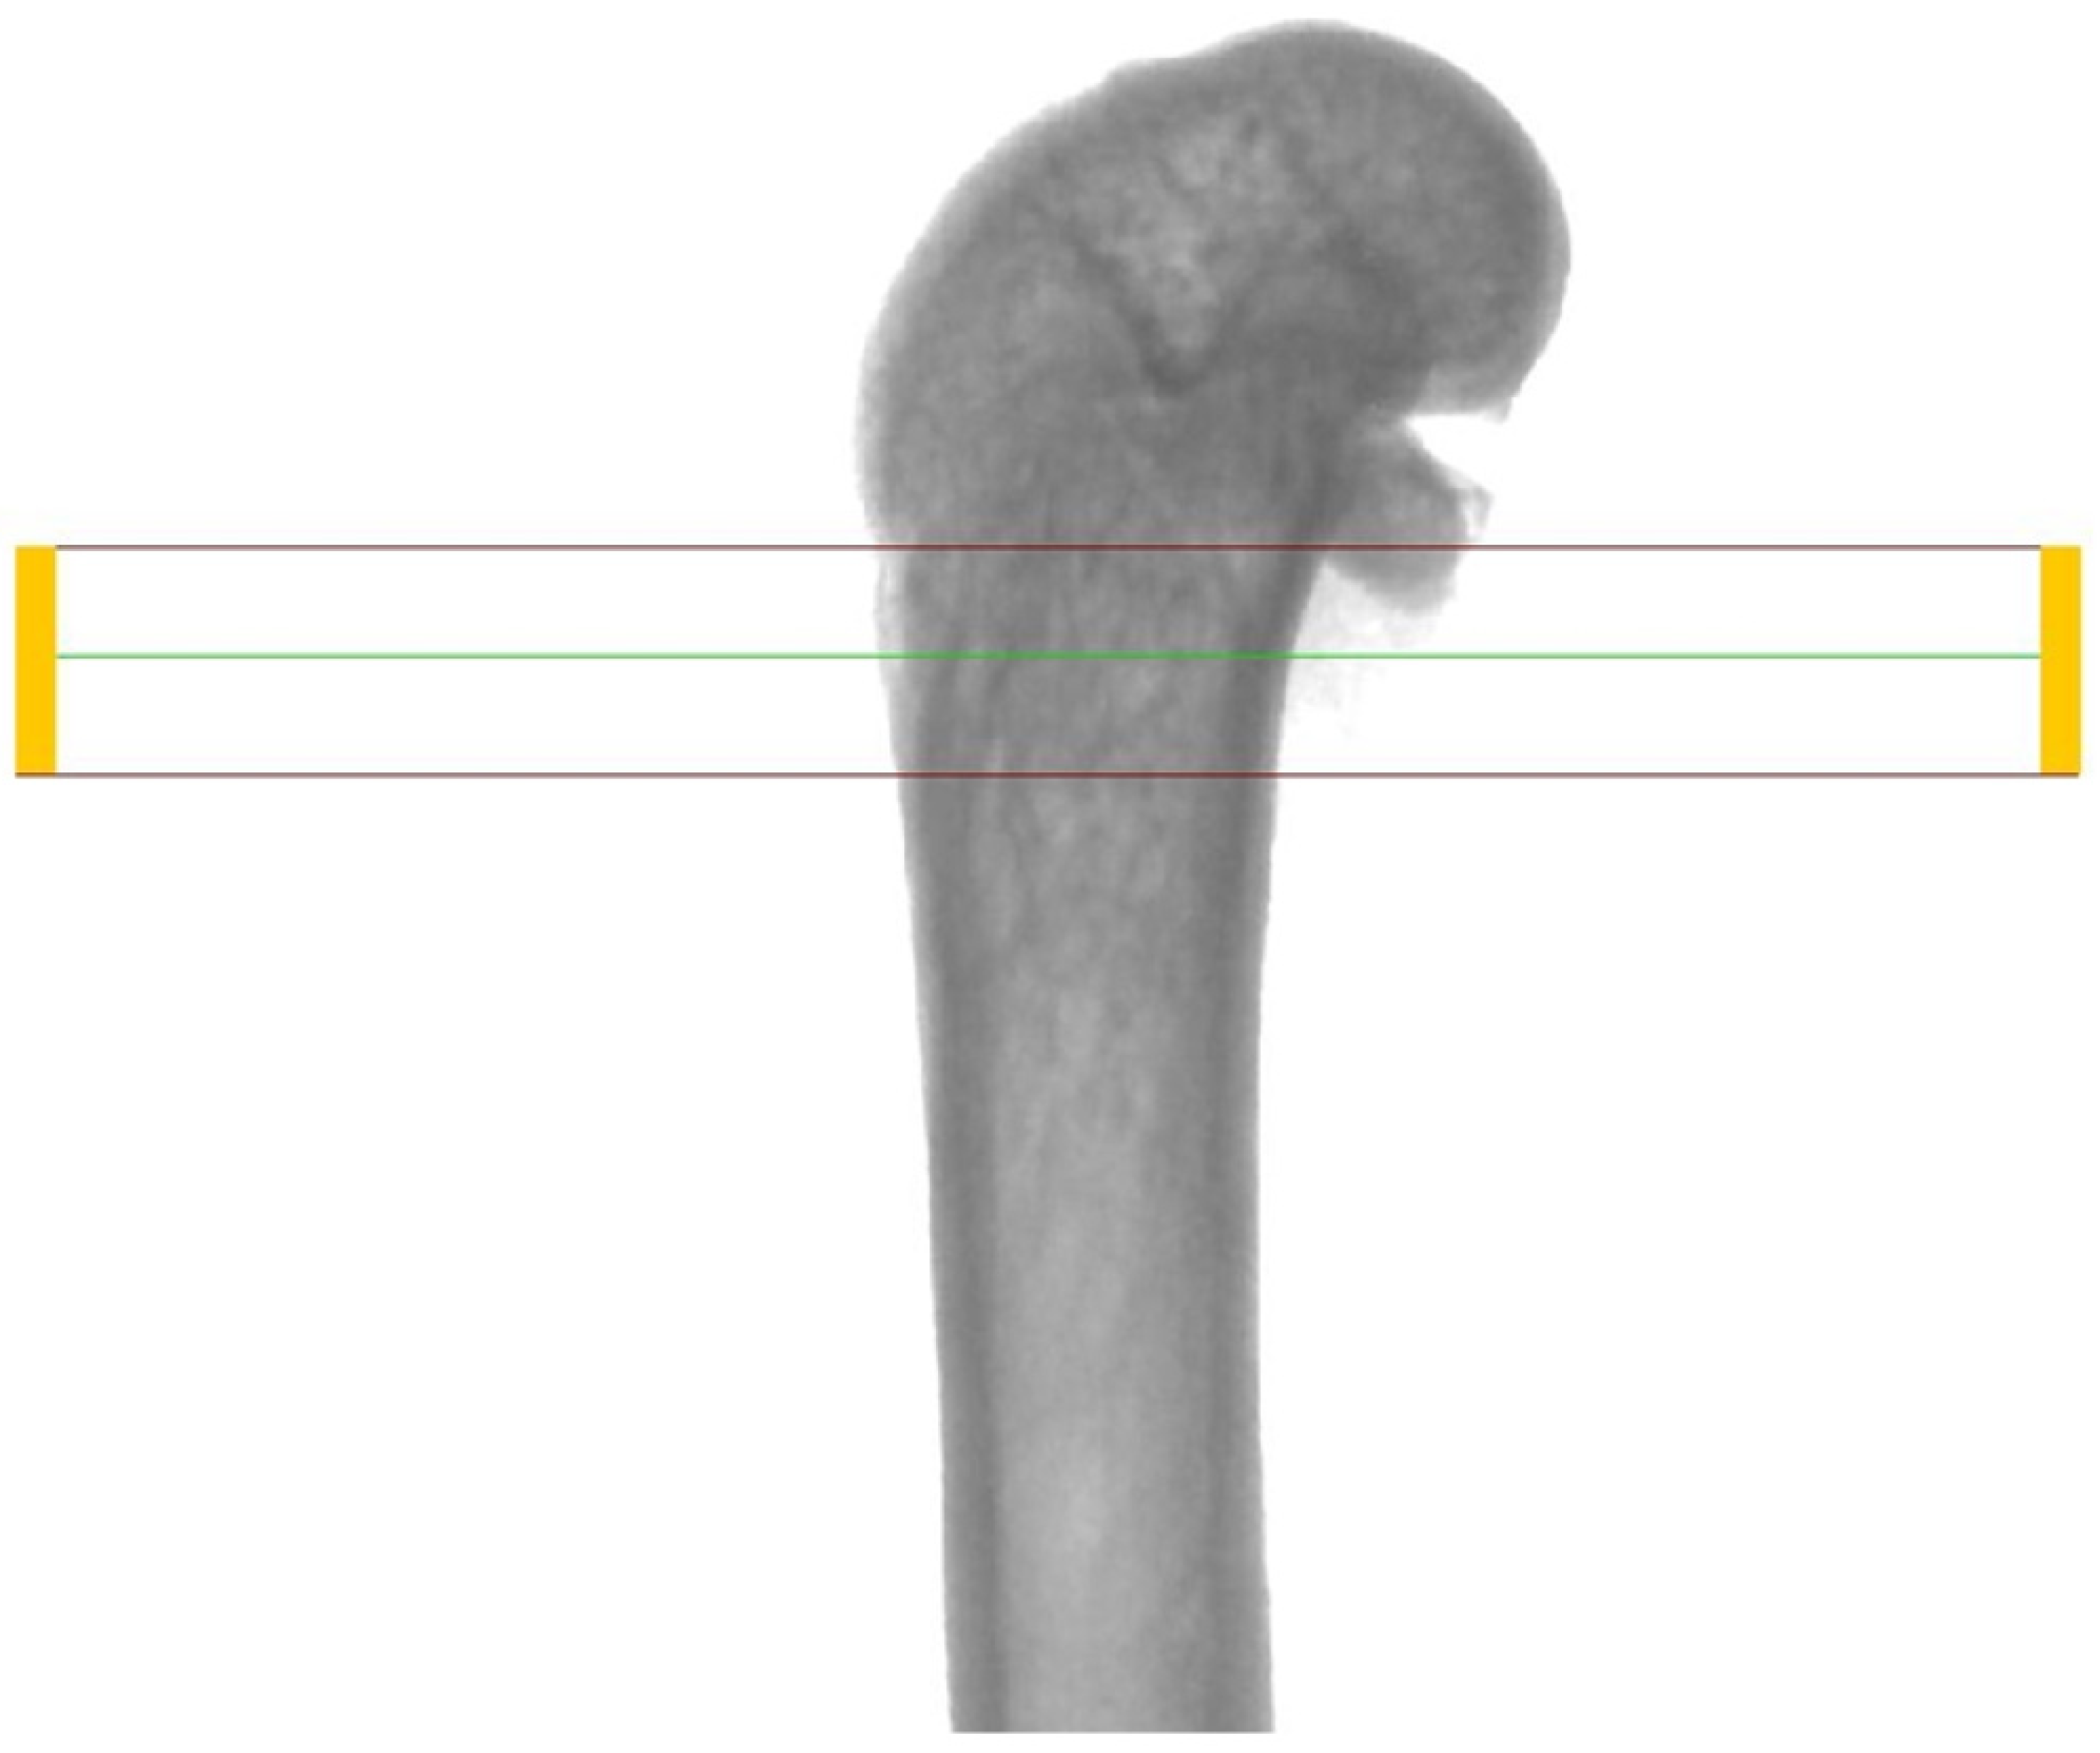

In order to evaluate the microarchitecture of bone tissue, the area of the distal metaphysis of the left femurs of all animals was subjected to microtomographic examination. After defrosting, the samples were placed on a centric stand in the center of the field of view of the microtomography chamber (Skyscan 1072, SkyScan, Antwerp, Belgium) and scanned (magnification 34×, Pixel 8.42, Rotation step 0.23, Exposure 1.9sec, and Gain 1). All of the samples were meticulously positioned so the mid-shaft of the bones was vertically straight and the orientation of the bones was consistent. Raw scans were reconstructed using the nRecon program (Skyscan, Belgium) and then thoroughly analyzed using the Ctan program (Skyscan, Belgium). An identical ROI (region of interest) was subjected to detailed morphometric evaluation. For the trabecular bone in all samples, a 100-slice cylinder was set in the central part of the distal epiphysis at a visual distance from the cortical bone, at the height of 85% of the bone length (Figure 1 and Figure 2). The analysis started at the most proximal end of the distal growth plate, which was visually identified in subsequent sections and taken as the reference point. In the ROI of each tested sample, the following microarchitectonic parameters were analyzed: percent of bone volume (BV/TV), trabecular thickness (Tb.Th), trabecular number (Tb.N), and trabecular separation (Tb.Sp). The surface of the cortical bone was assessed by subtracting the area whose outer border was the cortex’s inner circumference from the femur’s total surface at the level of the most proximal scan of the ROI from each group. Length measurements were measured from the left femur using a caliper. Representative micro-CT overview images are shown in Figure 3, Figure 4 and Figure 5.

Figure 1.

Region of interest (ROI) chosen for investigation (framed)—longitudinal view.